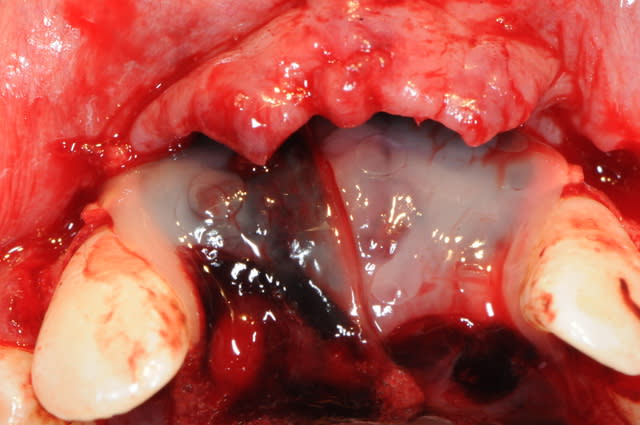

Et par dessus ? des granulés de biooss ? Par dessus le biooss ? Un steak de PRF ?

oui biobank et granules de biobank par dessus.

Je trouve que tu ne gagnes rien en épaisseur au niveau de la crête ( mais on ne vois pas bien avec le lambeau , tu as peut être assez ? ).

Pour juste combler les dépressions, tes deux vis en piquets de tente sans bloc auraient fait aussi bien.

Sans membrane collagène sous le PRF , tu ne crains pas de perdre tous tes granules ?

Oui et non la meilleure membrane étant le périoste, dans ce cas précis les scarifications sembleraient ne pas avoir été necessaires de par le defaut en dépression. Cette situation permet au périsote d'appliquer +++ et de tout maintenir.